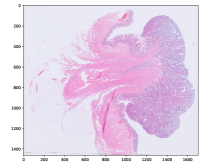

Refer to caption

(a) MSI negative

(b) MSI positive

(c) MSI negative

Figure 3: Three examples of diagnostic slides from the CancerScout Colon dataset. Slides are plotted with an optical magnification of 2.5.

2.1 The CancerScout Colon Data

For this study, we use 208520852085 diagnostic slides from 840840840 colon cancer patients. We have estimated the MSI status of all patients using clinic immunohistochemistry (IHC) based test. A total of 144144144 (17 %times17percent17\text{\,}\mathrm{\char 37\relax}) patients in the cohort are MSI positive. In addition, we have annotated tumor regions in 299299299 slides from 279279279 patients, with the open-source annotation tool EXACT [18]. We use these annotations to train a segmentation model for our reference two-stage approach. Ethics approval has been granted by University Medical Center Goettingen (UMG).

2.1.2 Image Data

The images are magnified H&E stained histological images of formalin-fixed paraffin-embedded (FFPE) diagnostic slides. Images are scanned with an isometric resolution of 0.250.250.25 microns/pixel, which corresponds to a microscopic magnification of 40 ×times4040\text{\,}\times. For all patients, a new slide was freshly cut, stained, and digitalized for this study. Figure 3 shows examples of those slides, we call them cnew slides. For 725725725 patients we have digitalized cold slides. These are archived slides which were cut and stained when the patient was initially treated. Each of the slides is from the same FFPE block as the corresponding cnew, located in very close proximity (about 2 µmtimes2micrometer2\text{\,}\mathrm{\SIUnitSymbolMicro m}). Those slides are used to augment training but not for evaluation. For 274274274 patients we have collected hnew slides. These are slides which only contain healthy tissue taken from the resection margins of the FFPE block. For 246246246 patients we have collected hold slides. These are slides which were cut and stained when the patient was initially treated, located in close proximity (about 2 µmtimes2micrometer2\text{\,}\mathrm{\SIUnitSymbolMicro m}) to the corresponding hnew slide We use those slides to increase the training data for our segmentation model.